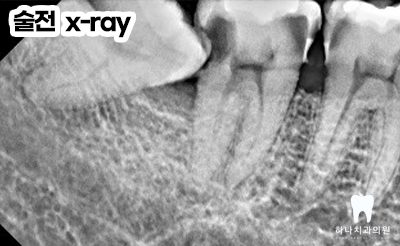

양쪽 아래 수평으로 매복되어 있는

사랑니가 관리되지 않아

바로 앞의 큰 어금니 뒤쪽으로

큰 우식을 공통적으로 가지고 있는

모습을 확인할 수 있었는데요.

오른쪽의 경우, 앞쪽에도 우식이

많이 진행된 상태였습니다.

따라서 양쪽에 매복되어 있는 사랑니를

발치하는데 심한 우식이 진행된 오른쪽의 경우

발치 후 임플란트, 왼쪽의 경우는 자연치 크라운을

진행하시기로 계획을 수립하였습니다.